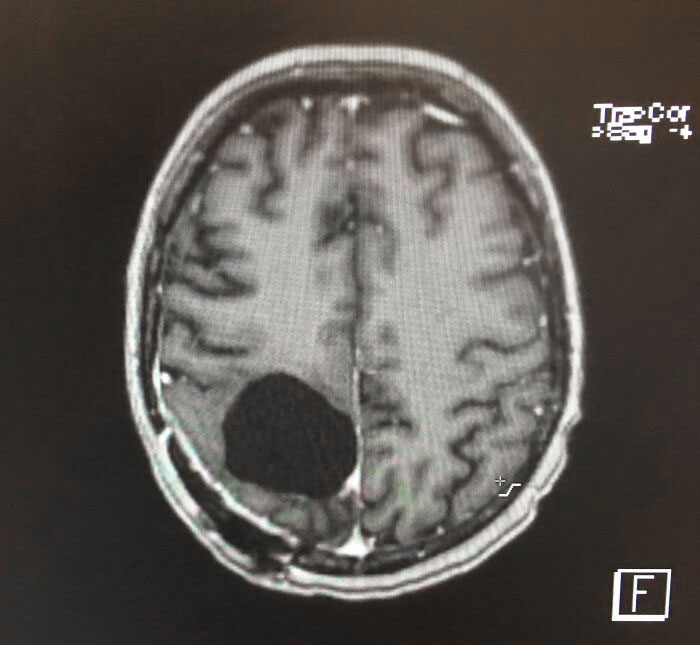

#1 Takto to vyzerá po tom, čo mi odstránili nádor na mozgu